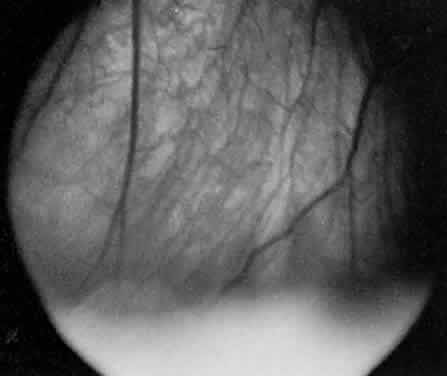

Retinal detachment, vitreous hemorrhage, optic disc swelling, and dragging of the optic disc vessels caused by contraction and neovascularization of cyclitic membranes occur in less than 10% of cases.13,52,53 Periphlebitis has been reported in about 21% of cases.52 Neovascularization of the optic disc53–55 and peripheral retina56 can also occur (Fig. 7). Coat's-like response has been reported in pars plantitis.57 Band keratopathy, glaucoma, and retinoschisis may develop as late sequelae in pars planitis.13

Fig. 7. Pars planitis. Fluorescein angiogram of neovascularization of the optic disc.